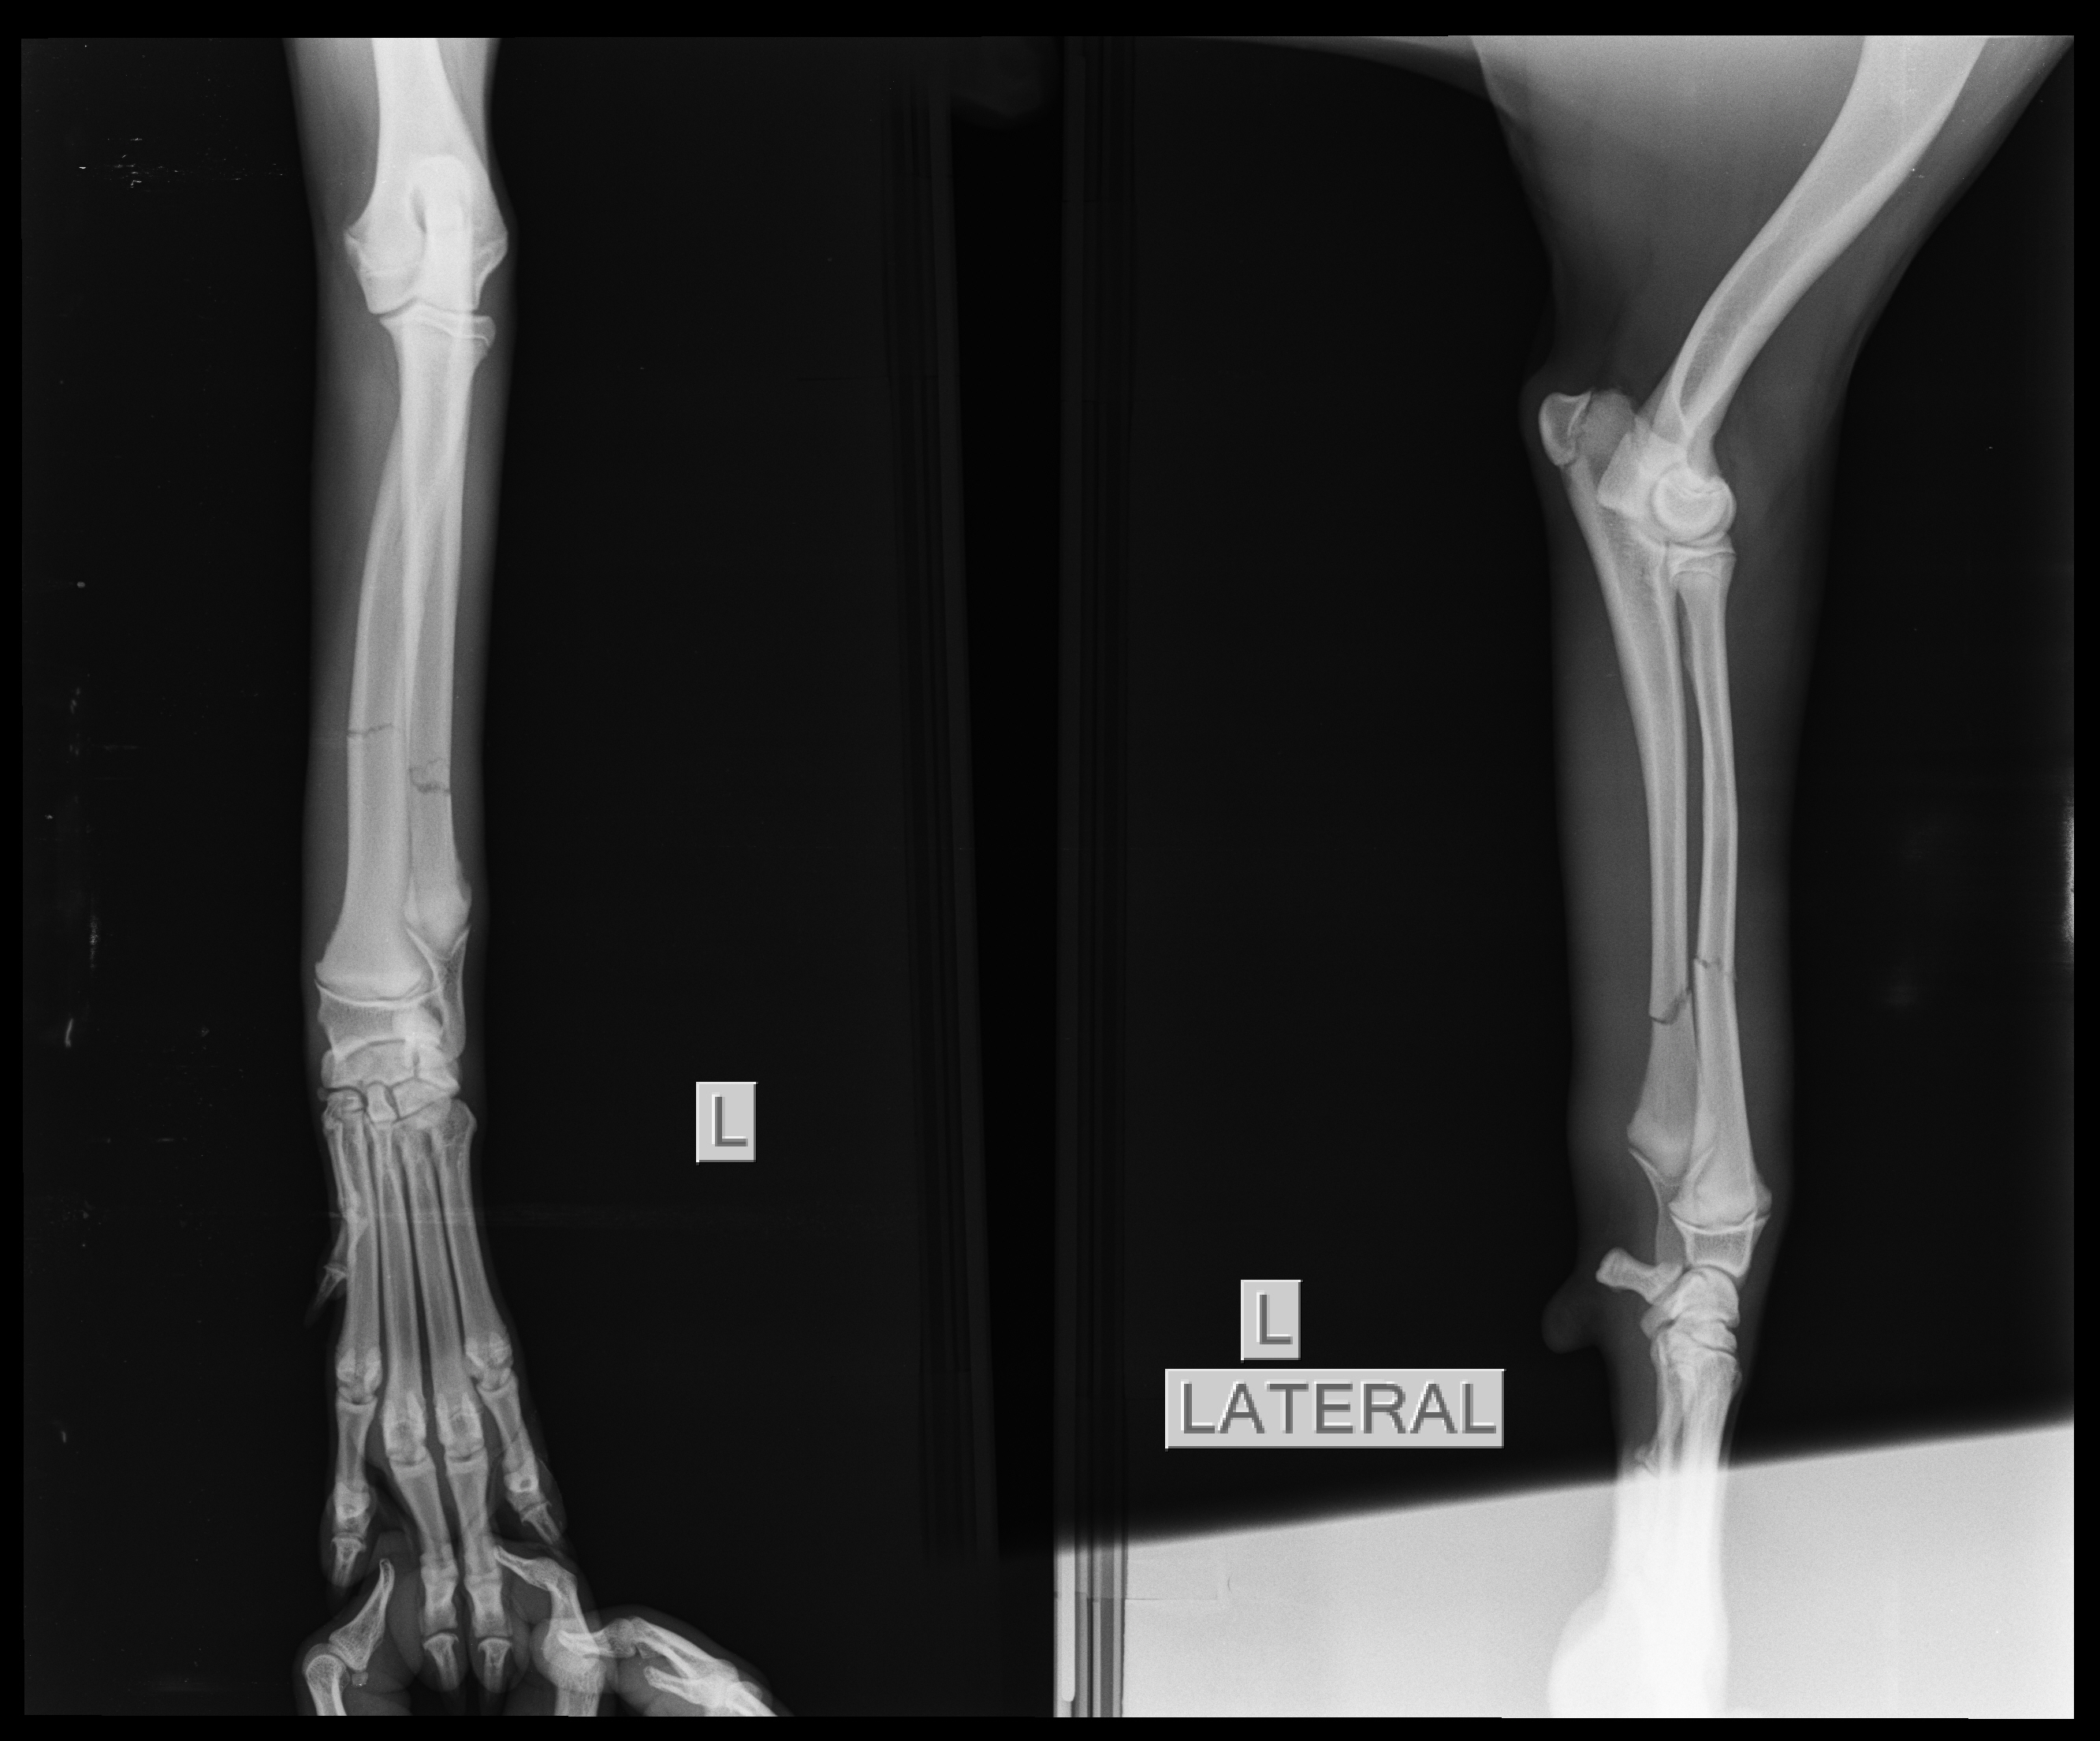

It doesn’t end. Ruku has a fracture.

She’s one of the pups I feed daily and she’s been limping since the few days. I thought with pain killers she will heal as she was otherwise doing all her regular masti.

This morning she looked in a lot of pain so I decided to take her to the vet. Got an xray done and she has a proper fracture.

A plaster has been put on her and she’s been moved into foster care.